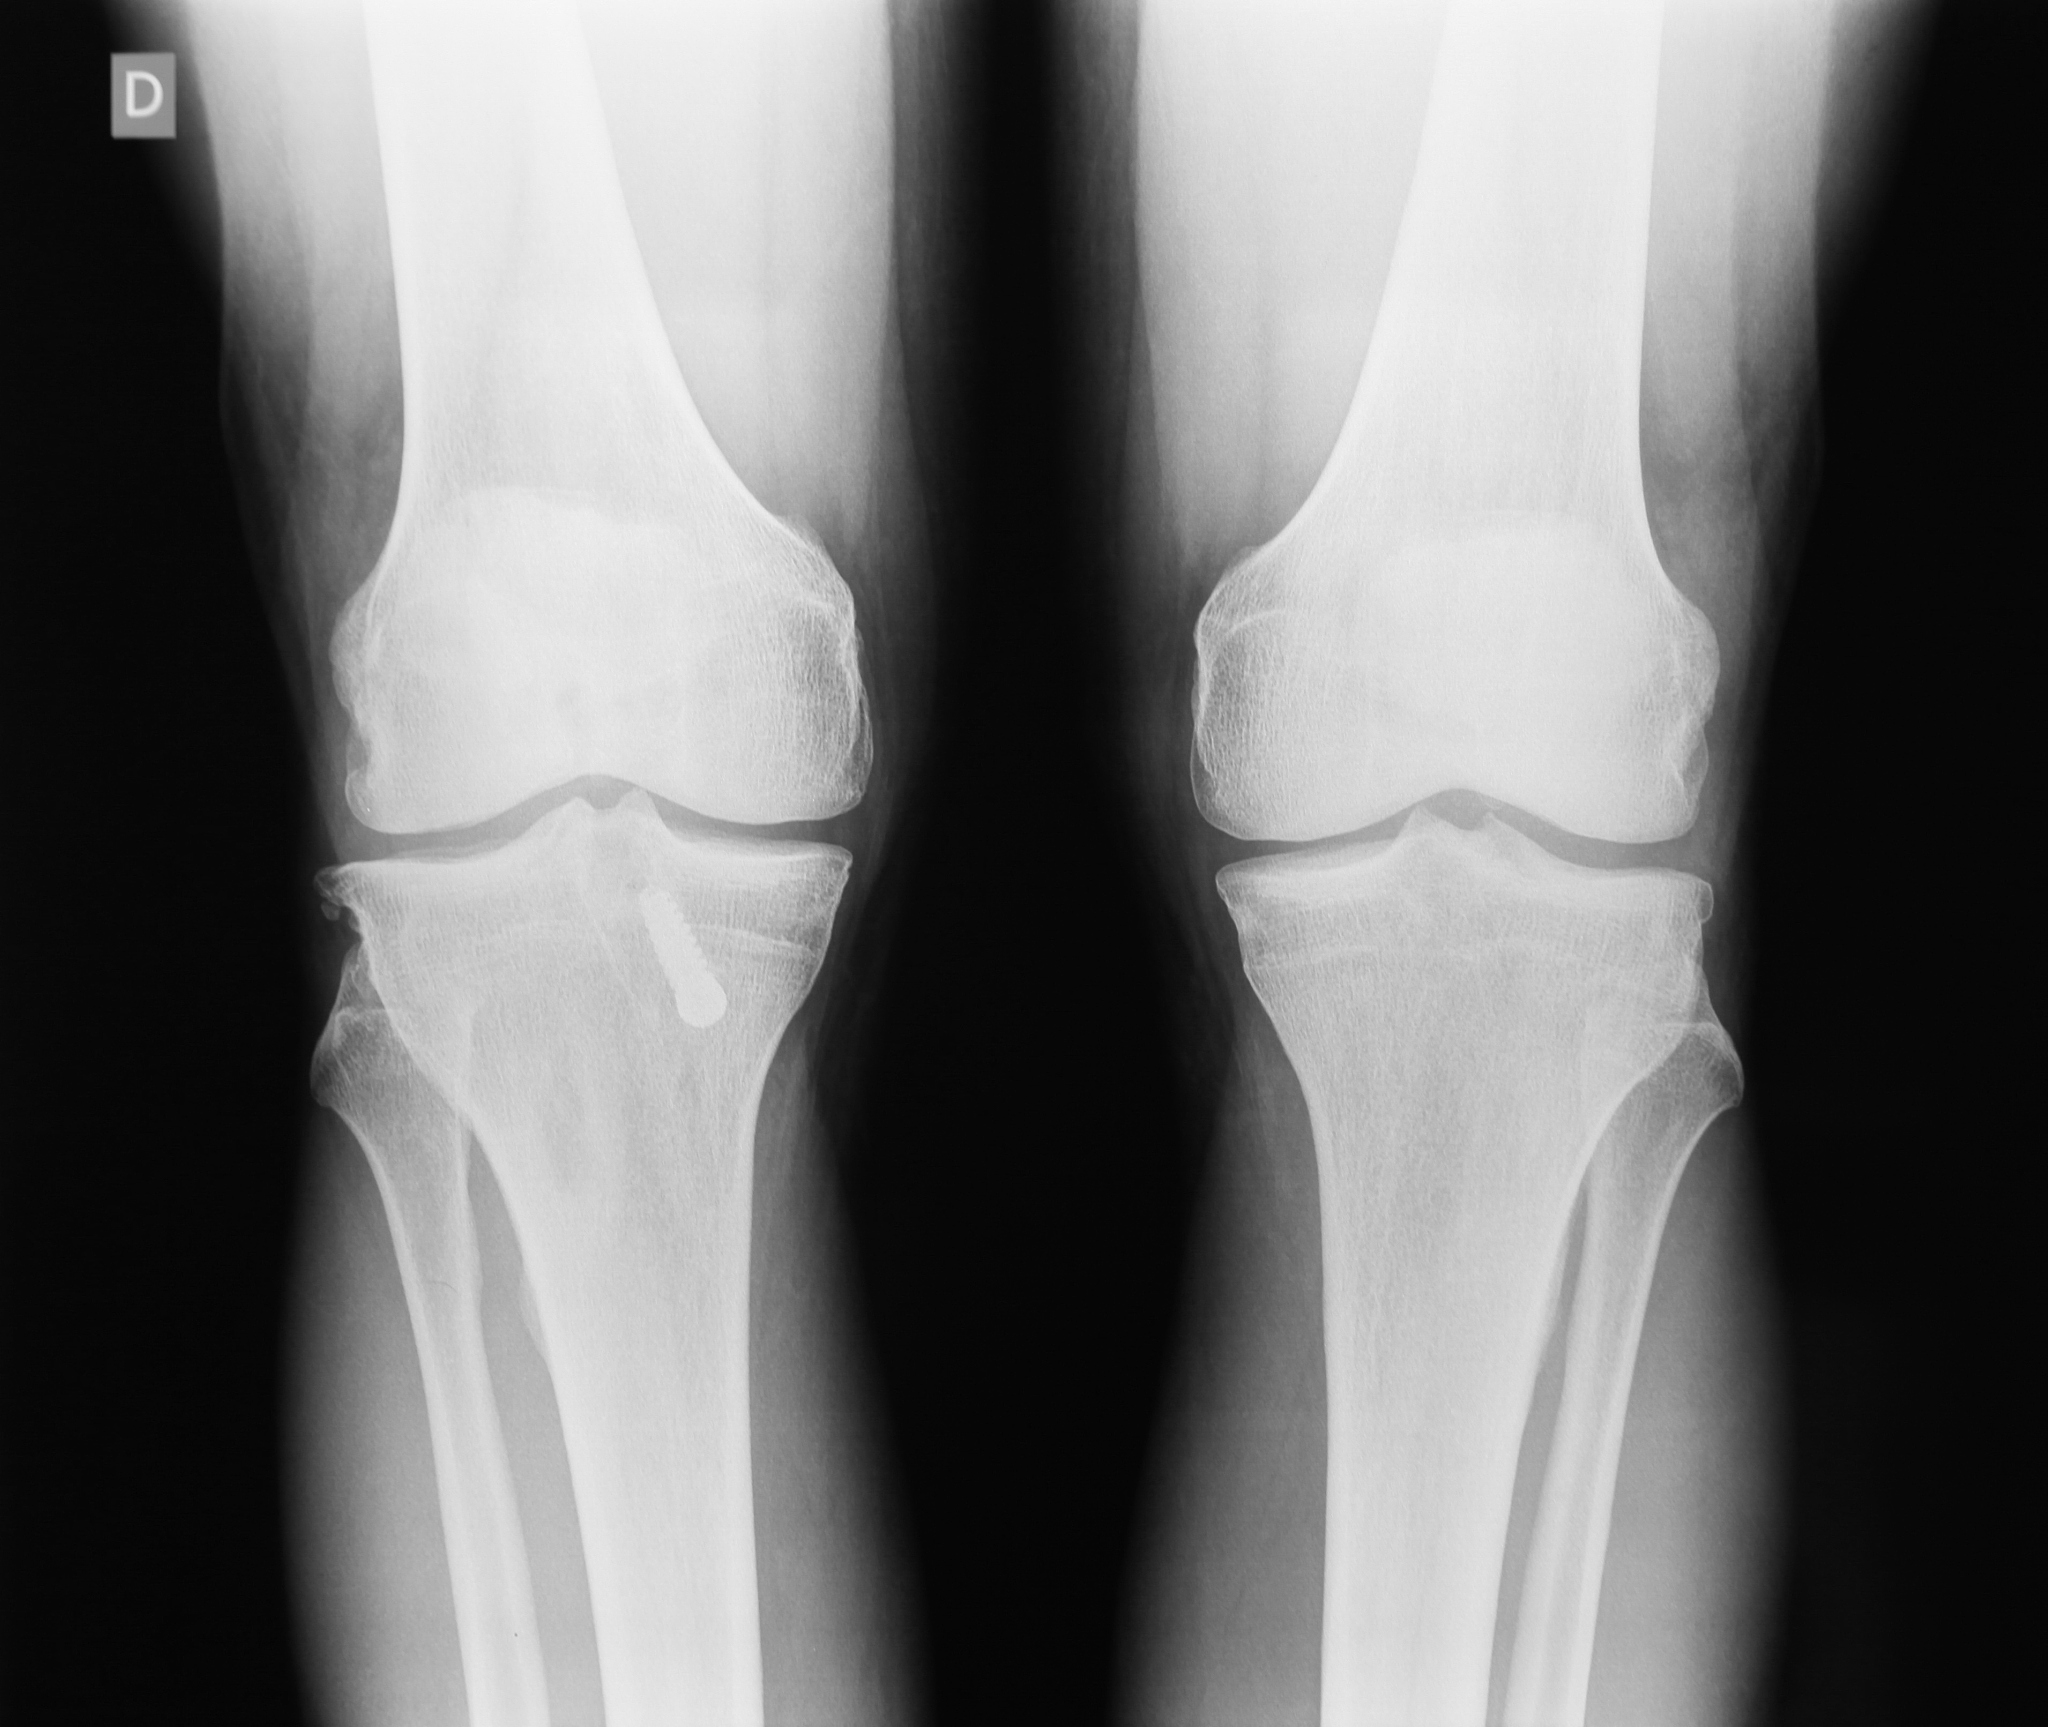

医生会根据病史、体格检查以及影像学检查来诊断后外侧塌陷性胫骨平台骨折。常用的影像学检查包括:

• X光片:可以清晰地显示骨折线、塌陷程度以及骨折碎片的位置。* CT扫描:能够提供更详细的三维图像,有助于评估骨折的复杂程度以及制定手术方案。